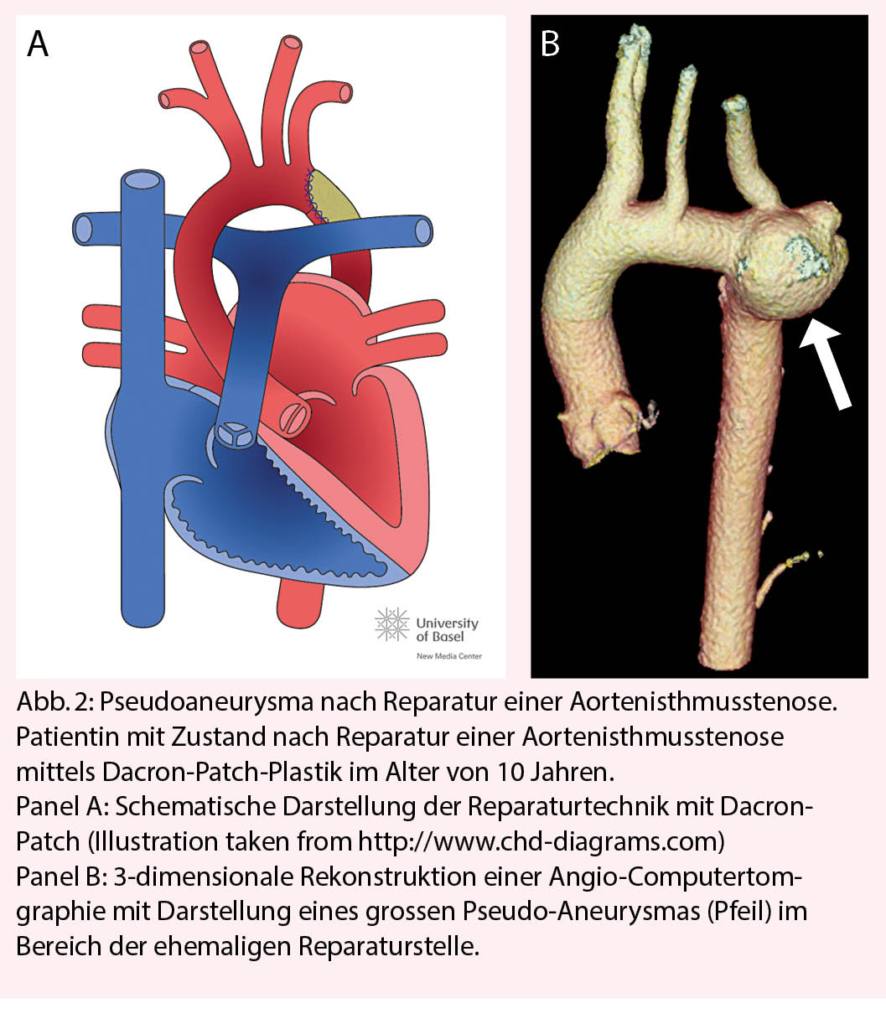

Patienten mit vorgängigen Operationen der Aorta haben ein erhöhtes Risiko für die Ausbildung von Aneurysmen und Pseudoaneurysmen. Dies gilt insbesondere für Patienten mit Bindegewebeerkrankungen (Marfan-Syndrom, Loeys-Dietz-Syndrom, etc.), aber auch Patienten mit reparierter Aortenisthmusstenose (Abb. 2). Bei diesen Patienten sind regelmässige Schnittbilduntersuchungen zur frühzeitigen Erkennung dieser Komplikation wichtig. Die Frequenz der Schnittbilduntersuchung richtet sich nach dem individuellen Risiko, insbesondere der verwendeten Operationstechnik der Aortenisthmusstenose und sollte je nach Situation mindestens alle 5-10 Jahre erfolgen.